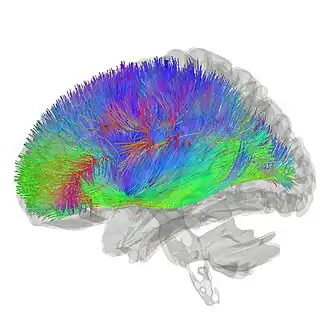

![]() Tractography showing corticostriatal connections | |